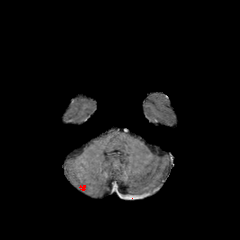

Objectives: This work aims to explore the impact of multicenter data heterogeneity on deep learning brain metastases (BM) autosegmentation performance, and assess the efficacy of an incremental transfer learning technique, namely learning without forgetting (LWF), to improve model generalizability without sharing raw data. Materials and methods: A total of six BM datasets from University Hospital Erlangen (UKER), University Hospital Zurich (USZ), Stanford, UCSF, NYU and BraTS Challenge 2023 on BM segmentation were used for this evaluation. First, the multicenter performance of a convolutional neural network (DeepMedic) for BM autosegmentation was established for exclusive single-center training and for training on pooled data, respectively. Subsequently bilateral collaboration was evaluated, where a UKER pretrained model is shared to another center for further training using transfer learning (TL) either with or without LWF. Results: For single-center training, average F1 scores of BM detection range from 0.625 (NYU) to 0.876 (UKER) on respective single-center test data. Mixed multicenter training notably improves F1 scores at Stanford and NYU, with negligible improvement at other centers. When the UKER pretrained model is applied to USZ, LWF achieves a higher average F1 score (0.839) than naive TL (0.570) and single-center training (0.688) on combined UKER and USZ test data. Naive TL improves sensitivity and contouring accuracy, but compromises precision. Conversely, LWF demonstrates commendable sensitivity, precision and contouring accuracy. When applied to Stanford, similar performance was observed. Conclusion: Data heterogeneity results in varying performance in BM autosegmentation, posing challenges to model generalizability. LWF is a promising approach to peer-to-peer privacy-preserving model training.